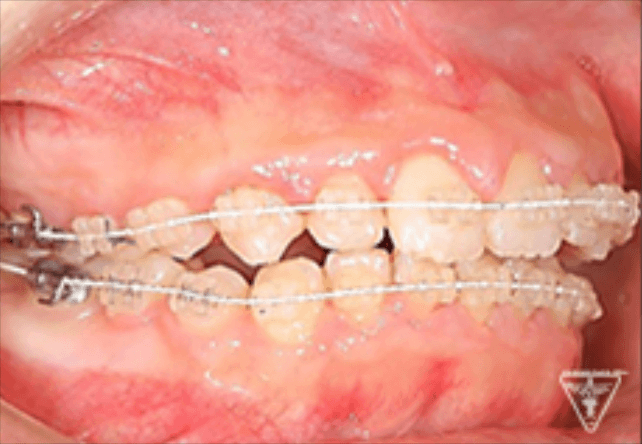

矯正器具 装着時の治療過程

後期